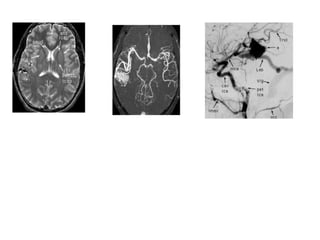

Multiple aneurysms in a 54-year-old woman.

Multiple aneurysms ina 54-year-old woman.

3D TOF MRAdemonstrates a 6 mm aneurysm arising from the basilar artery tip and projecting anteriorly

MCA aneurysm seen InT2W MRI as flow void MCA aneurysm seen In CECT

• #70 23 yr young female presented with post partum rt hemiparesis with altered sensorium, on improvement had aphasia, T2 and flair show multiple hyperintensities in lt parietooccipital region, corrosponding ,with restrictn on DWI and low ADC value s/o infarctn, corrosponding MRA , lt MCA not visualised s/o thrombosis.